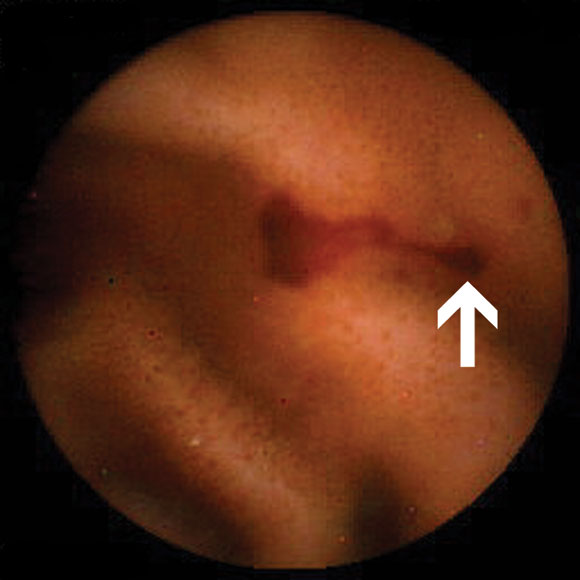

In 47 patients with OGB, abnormal findings (Box 2A) were detected in 32 (68%). Four had abnormalities detected in the stomach, and one in the caecum. Eight had abnormalities judged to be within reach of push enteroscopy. Eighteen of the 47 (38%) patients had a change in management as a result of capsule endoscopy (Box 3).

Of the nine patients referred for investigation of small-bowel Crohn's disease, none had been taking non-steroidal anti-inflammatory drugs (NSAIDs) before onset of their symptoms. Small-bowel erosions or ulcers (Box 2B) were seen in seven of these nine patients. Enteroclysis demonstrated mucosal irregularity in two of the seven patients with abnormal findings on capsule endoscopy. Management was changed in five of the nine patients. One patient was lost to follow-up. Changes in management are summarised in Box 4.